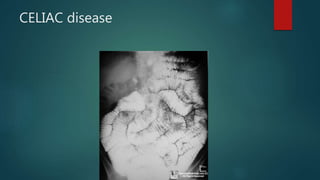

CELIAC disease